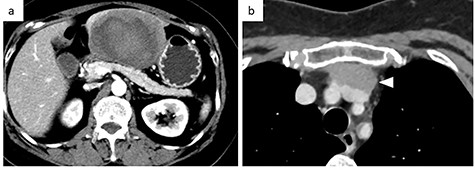

A 56-year-old woman presented to another hospital with acute abdomen. Computed tomography (CT) examination demonstrated a tumor 10 cm in diameter that protruded from the left lateral segment of the liver, with evidence suggestive of rupture of the liver tumor (Fig. 1). Since the patient was in good general condition, she was referred to our hospital for further evaluation. Her blood biochemical parameters when she was referred to our hospital were hemoglobin: 11.6 g/dl, albumin: 3.4 g/dl, γ-globulin: 18.5% and anti-acetylcholine receptor antibody: <0.3 nmol/L. Dynamic CT presented a liver tumor 10 cm in diameter, which was located at the left lateral segment of the liver, with a clear margin. A mass with an irregular margin was also identified in the anterior mediastinum (Fig. 2). On percutaneous angiography, since obvious extravasation of the contrast medium could not be identified, the arteries of the left lateral segment were embolized to prevent re-bleeding. Although a definitive preoperative diagnosis could not be made using magnetic resonance imaging (MRI) (Fig. 3), fluorodeoxyglucose positron emission tomography (FDG) showed increased FDG uptake in both the hepatic and anterior mediastinal tumors (Fig. 4). Although the liver tumor was suspected to be metastasis secondary to a thymoma based on the clinical findings, percutaneous tumor biopsy was performed to confirm the pathological diagnosis. The biopsy suggested malignant T-cell lymphoma or metastatic thymoma. In order to prevent re-rupture of the hepatic tumor, to confirm the pathological diagnosis and to potentially achieve a curative resection, the patient underwent laparoscopic left lateral segmentectomy (Fig. 5). Although the tumor was found to be adherent to the stomach, blunt dissection was possible. In addition, no peritoneal dissemination was detected. The surgical duration was 212 min and estimated blood loss was 50 ml. The liver tumor was pathologically diagnosed as metastatic thymoma type AB (Fig. 6). The patient’s postoperative course was uneventful and she subsequently underwent radical thymectomy 3 months after the liver resection. The thymic tumor was pathologically diagnosed as thymoma type B2. Currently, 30 months after thymectomy, she remains free from tumor recurrence.

Contrast-enhanced CT. (a) Abdominal CT: a solitary liver tumor, 10 cm in diameter, was located in the left lateral segment of the liver. The tumor had a clear margin, with tumor enhancement in both the arterial and portal phases. (b) Chest CT: an enhanced tumor with an irregular margin was detected in the anterior mediastinum. The tumor had a maximum diameter of 4.5 cm.